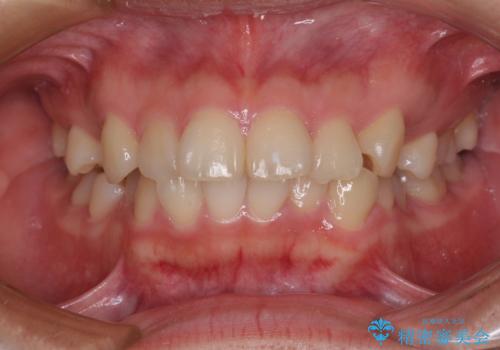

- 口元の閉じにくさを気にして来院された患者様です。

地元で矯正治療を始める予定で上顎左右第1小臼歯2本を抜歯したものの、その後転居したため治療が滞っているとのことでした。

上下ともに歯列が前方に突出していたため、上下左右の第一小臼歯4本を抜去する方針(既に上顎は抜歯されています)で、ワイヤー装置による矯正治療を行うこととしました。